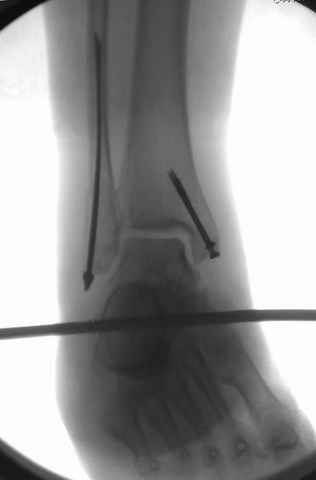

Фиксация переломов малоберцовой: пластина, интрамедуллярные конструкции или tension band technique.

Если перелом низкий и поперечный, делаю интрамедуллярно, спицей или интрамедуллярным штифтом, при косых переломах пластина (antiglide technique), при пользовании аппарата Илизарова спицу провожу через тибиа-фибула.

На снимках варианты фиксации малоберцовой:

№ 2-5 при огнестрельном переломе